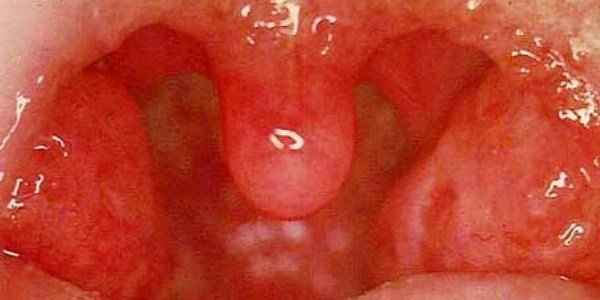

При здоровом горле прежде всего человек не испытывает болезненные ощущения при глотании, а также першение. Но иногда болезнь начинает прогрессировать без видимых симптомов. Как же должно выглядеть горло в нормальном состоянии?

Здоровое горло:

- бледно-розового цвета, без покраснений и красных пятен;

нет никаких пузырьков и белых комочков;

- миндалины нормальных размеров, без припухлостей и резких выступов;

- язык и миндалины должны быть без белого или серого налета;

- на задней стенке горла отсутствует расширенная венозная сетка или фолликулы;

- нет отечности горла.

Вот так, как на фото выглядит здоровое горла. Бывают редкие случаи, что физиологическое строение горла некоторых людей имеет большие миндалины и это не является патологией.